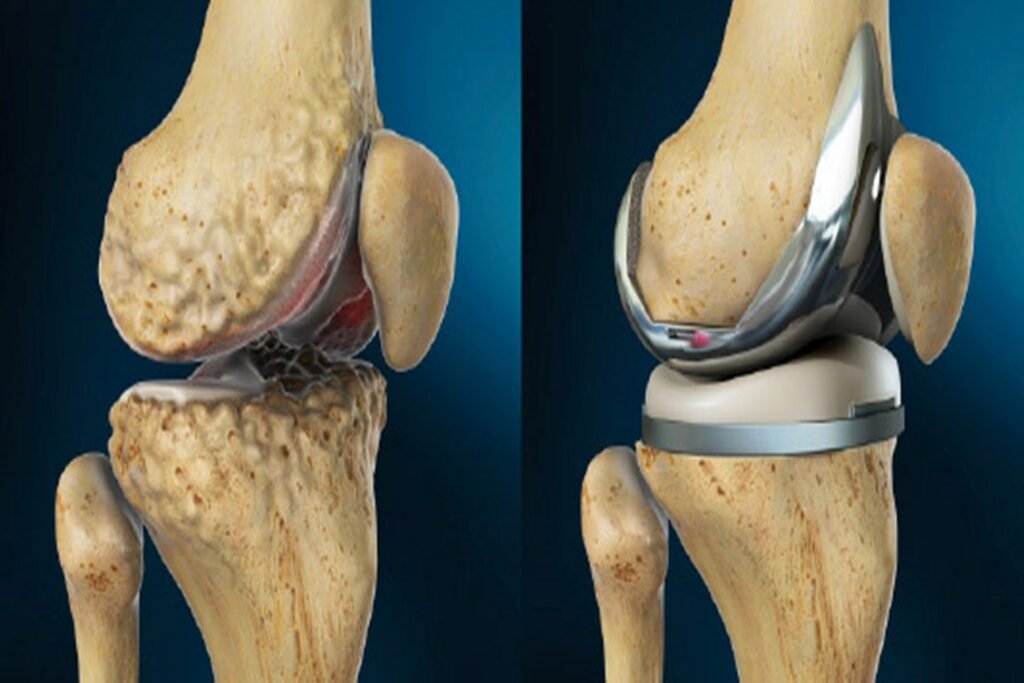

عملية تغيير مفصل الركبة هي إجراء جراحي يتم فيه استبدال الأجزاء التالفة من مفصل الركبة بمكونات صناعية مصممة بدقة لتحاكي حركة المفصل الطبيعي. وذلك قد يكون استبدالاً كاملاً للمفصل، أو استبدالاً جزئيًا بتغيير الأجزاء المتضررة من المفصل بشكل جزئي في بعض الحالات، وذلك حسب حالة المريض. ويُنصح بها في حالات:

تشير الدراسات العالمية إلى أن جراحات استبدال مفصل الركبة تحقق نسب نجاح مرتفعة تتجاوز 90% خلال 15–20 سنة من عمر المفصل الصناعي، وذلك مع تحسن ملحوظ في جودة الحياة والقدرة على الحركة. تعرف على نسبة نجاح عملية تغير مفصل الركبة لكبار السن.